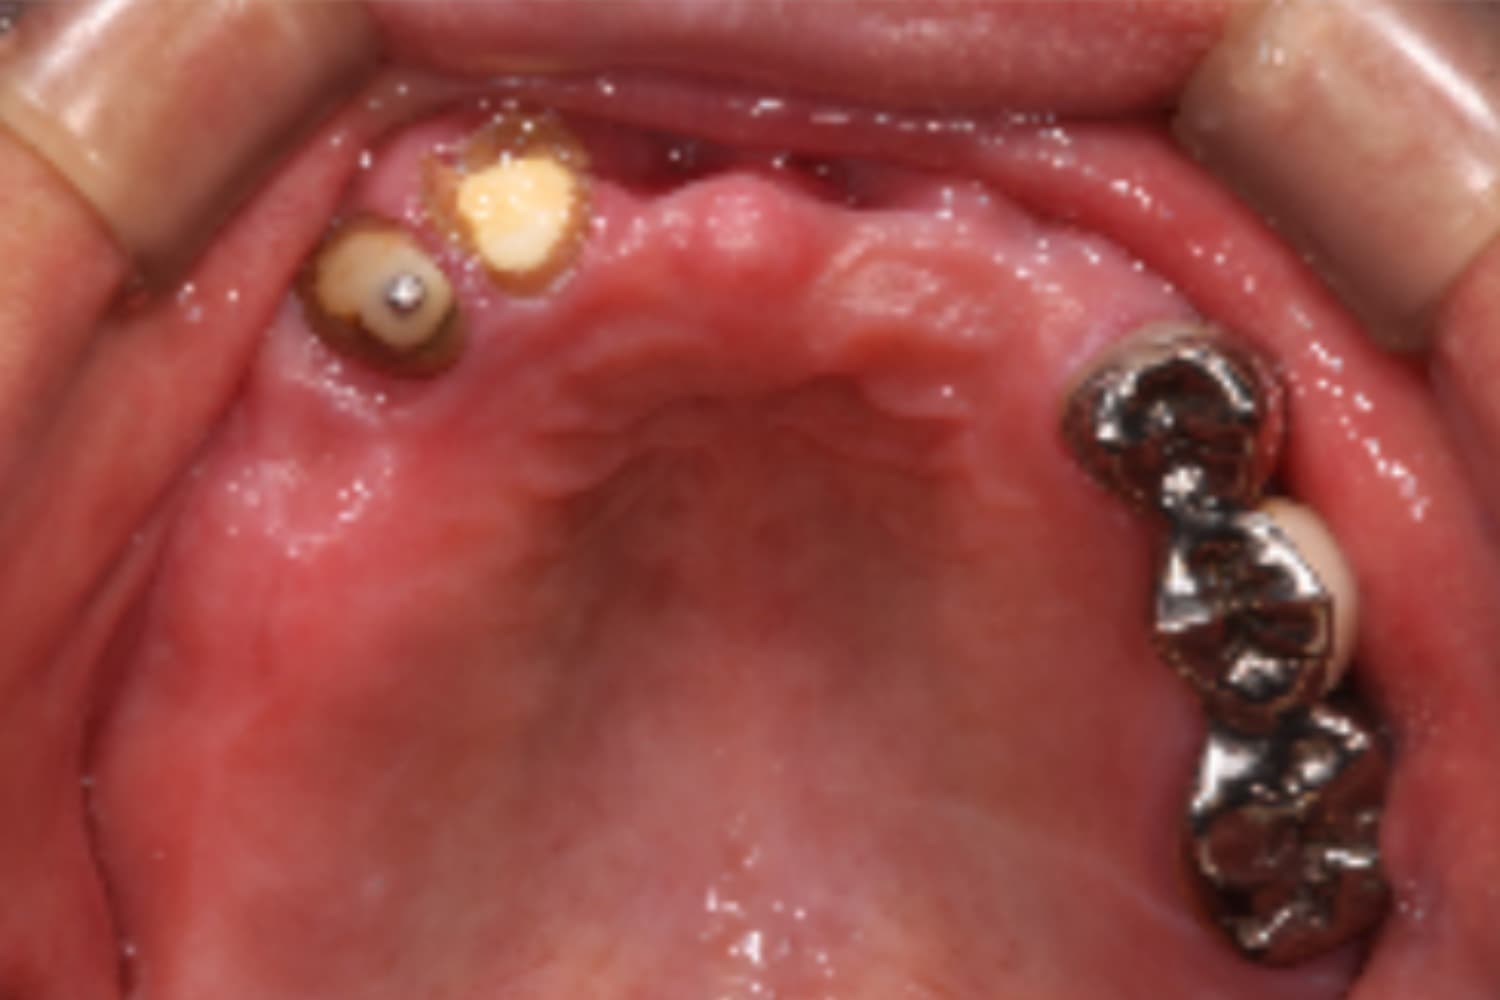

上顎すべてのインプラント治療

Before

After

上顎をインプラント7本で治療

主訴

上顎欠損部にインプラント治療希望

治療期間

18カ月

治療回数

26回

費用

3,450,000円

副作用・リスク

・噛み合わせの崩壊により、治療途中に顎の痛みや顎関節症様の発症リスクがあります。